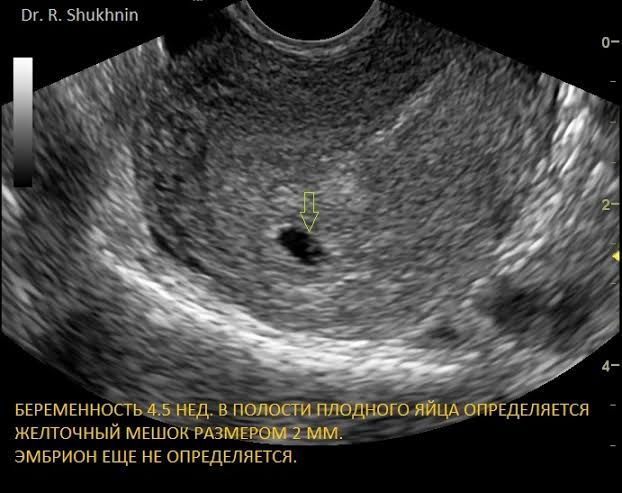

Вот так выглядит на супер раннем сроке, как точечка.

Вот так чуть попозже (~5 недель).

В 6 недель при здоровой беременности будет эмбрион в виде такого кольца и там уже будет биться сердечко.